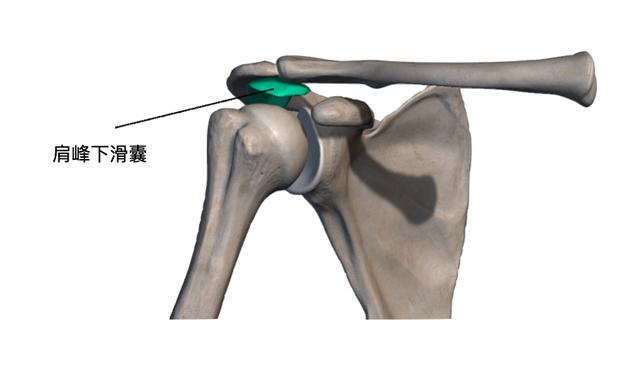

并且在这之间有滑囊来避免活动时肌腱与肩峰之间的直接撞击

图片尺寸1051x516